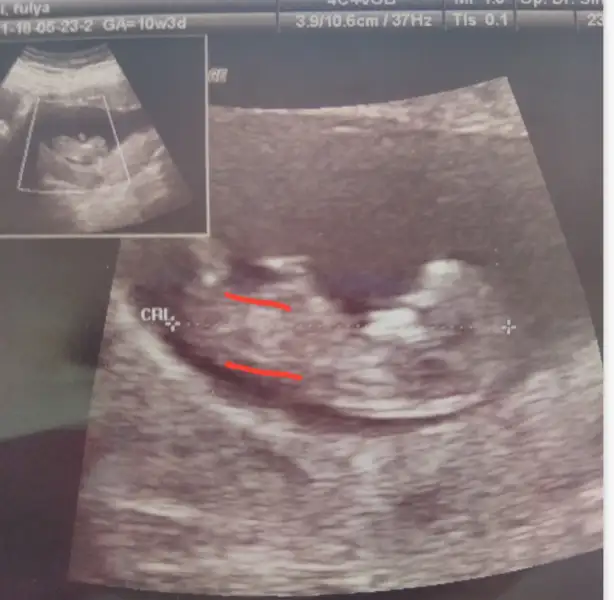

Canımmm çok sevindim valla maşallah maşallah ikinize de :) Bu da erkek sanki sen ne hissediyorsun :)

Banada kız gibi geldi sanki nubu paralel goruruyorum doğru görüyorsam tabi :)Canımmm çok sevindim valla maşallah maşallah ikinize de :) Bu da erkek sanki sen ne hissediyorsun :)

Banada kız gibi geldi sanki nubu paralel goruruyorum doğru görüyorsam tabi :)

Ben de göremedim sanki ya o yuzden erkektir diye tahmin ettim :) çok heycanlı benimkini atsam size aaaa kız buuu dersiniz ama 9+6 daydım ve genital tüberkül birbirine çok benziyormuş 11. Hafta dolana kadar :)20

Benziyor evet ama doktorlarda nuba bakarakta tahmin ediyorlar bir kaç doktor böyle tahmin ettiğini söylediBen de göremedim sanki ya o yuzden erkektir diye tahmin ettim :) çok heycanlı benimkini atsam size aaaa kız buuu dersiniz ama 9+6 daydım ve genital tüberkül birbirine çok benziyormuş 11. Hafta dolana kadar :)